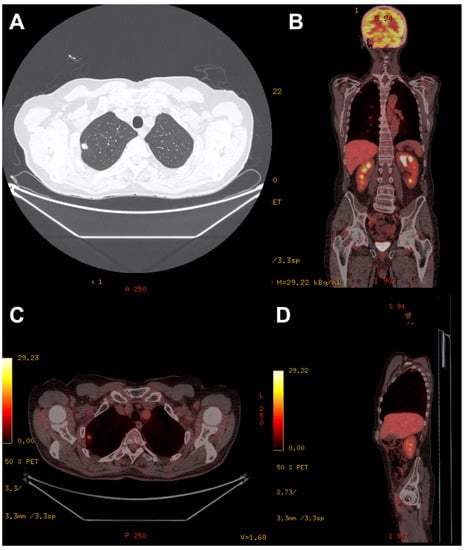

2. Case 1